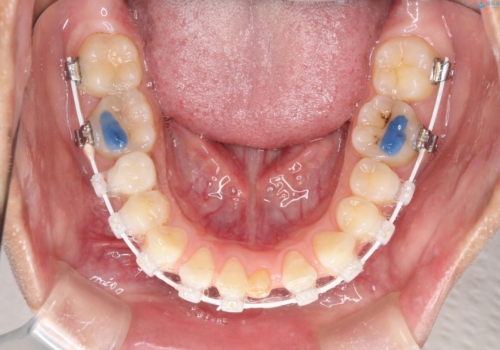

- 矯正装置

- 審美装置

- 歯と歯の間に隙間があることを主訴に来院されました。

短期間での治療終了を希望され、ワイヤー矯正にて治療を行い1年ほどで治療を終了しております。